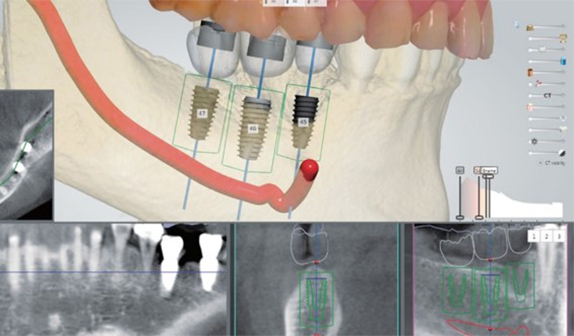

계획된 대로 심는 네비게이션 임플란트

우리에게 올바른 길을 알려주는 네비게이션처럼 디지털 기술을 통해 최적의 수술 경로를 알려주는 네비게이션 임플란트. 3D 모의 수술을 통해 식립 위치를 정확하게 파악하고 오차 없이 식립 가능한 체계적인 디지털 임플란트 입니다.

• 치료기간 단축

• 높은 정확도 & 안정성

• 적은 통증 빠른 회복

• 전신질환자 고령자 가능